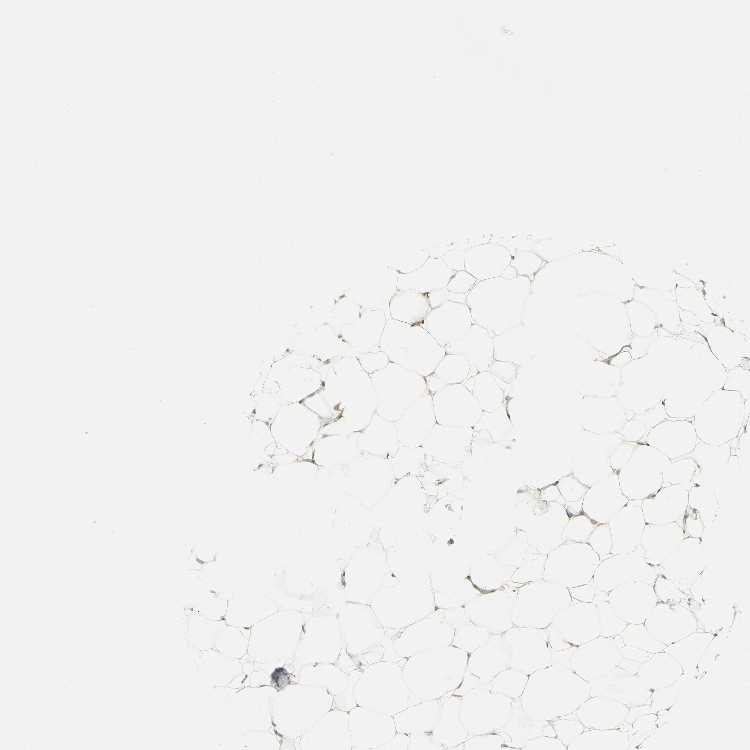

SOFT TISSUE 1 - Antibody stainingi

Antibody staining in the annotated cell types in the current human tissue is reported as not detected, low, medium, or high, based on conventional immunohistochemistry profiling in selected tissues. This score is based on the combination of the staining intensity and fraction of stained cells.

Each image is clickable and will lead to virtual microscopy that enables deeper exploration of all samples and also displays staining intensity scores, fraction scores and subcellular localization as well as patient and tissue information for each sample.

Antibody HPA006916Antibody HPA010568Antibody CAB017617

Chondrocytes -Not detected-

Fibroblasts Not detectedNot detectedMedium

Peripheral nerve Not detectedNot detectedMedium